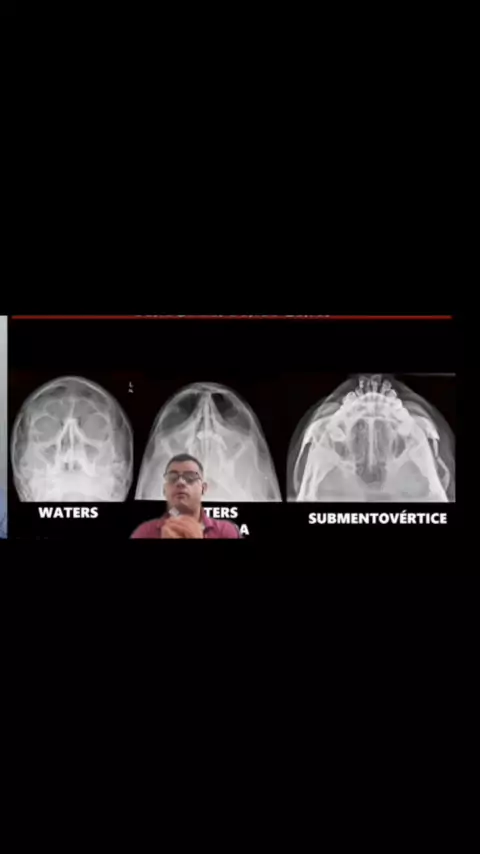

Analisando rx de coluna lombar ap e perfil. tr.Ítalo Michael crtr 07244t #orgulhonerd #radiologia #viral

Análise radiográfica. radiografia de mãos. tr° Italo Micharel. CRTR 07244T #interessante #orgulhonerd #radiologia #viral